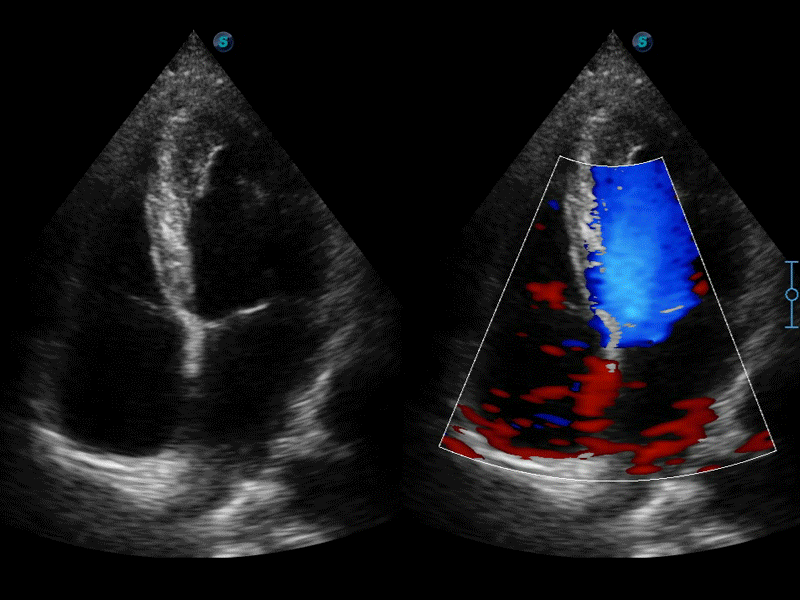

临床图像

• SR Flow高分辨率血流成像技术

高分辨率血流成像技术提高了对低速血流信号的检测能力。在提高空间分辨率的同时,也克服了血流外溢现象,为用户提供更加真实的血流动力学信息。